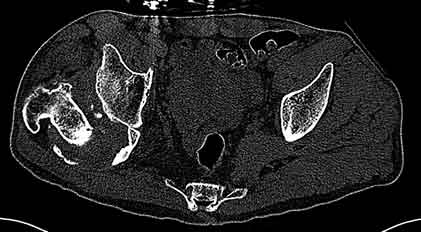

Уважаемые коллеги, пациент 30 лет, 4 года назад попал под поезд, ампутация обеих голеней в в/3, подвздошный вывих бедра (теперь застарелый). несмотря на такую ситуацию, пациент вполне прилично ходит и объем движений в неоартрозе близок к неповрежденной стороне. Основная жалоба - боль при нагрузке и в покое. Планируем двухэтапное лечение: резекция шейки, мобилизация проксимального отдела бедра, низведение бедра АВФ, вторым этапом б/ц эндопротезирование. Как поступить с головкой, вроде бы при протезировании можно будет обойтись без пластики, или ошибаюсь? Оставить ее там, где она есть? Другие варианты лечения.